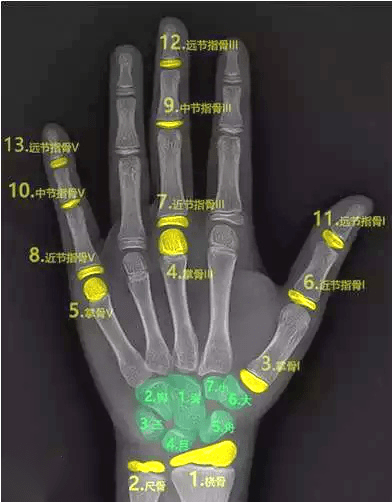

三、骨齡測(cè)試法

骨齡是骨骼年齡的簡(jiǎn)稱,比實(shí)際年齡更能反映人體骨骼的成熟度。

一般是拍攝左手腕部的X線片,觀察指骨、腕骨、橈骨、尺骨下端的骨化中心出現(xiàn)的時(shí)間、面積大小、判斷骨骼實(shí)際發(fā)育程度,來(lái)確定骨齡。

如果骨齡小于生活年齡1歲以上,提示有生長(zhǎng)激素缺乏癥的可能;骨齡大于生活年齡1歲以上的孩子可能早熟,往往其成年的最終身高反而受損。

因此骨齡異常需要盡早到專業(yè)醫(yī)療機(jī)構(gòu)就診,必要時(shí)進(jìn)行醫(yī)學(xué)干預(yù)和藥物治療。